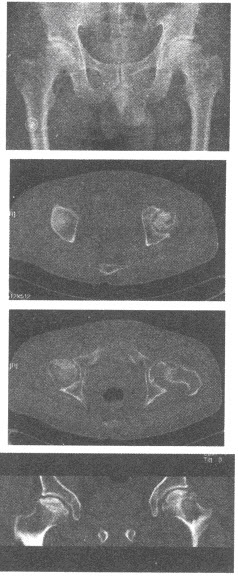

患者,男性,42岁,髋部疼痛,CR及CT图像如下,应诊断为()

A:髋关节结核

B:股骨头缺血坏死

C:股骨头退变性囊肿

D:骨岛

E:骨质疏松